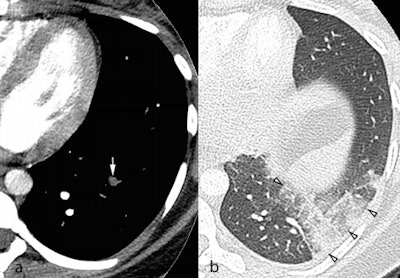

In consensus, two blinded radiologists reviewed the CTPAs of 229 patients with regard to PE, alternative diagnoses, and technical quality. The researchers found that 16 patients (7%) had PE, 144 (62.9%) had no abnormal findings, and 69 (30.1%) had an alternative diagnosis such as consolidation, other pulmonary opacities, pleural effusion, and basal atelectasis.

Among the 213 patients without PE, 35 (16.4%) had a single alternative diagnosis, while 34 (16.0%) had multiple alternative diagnoses.